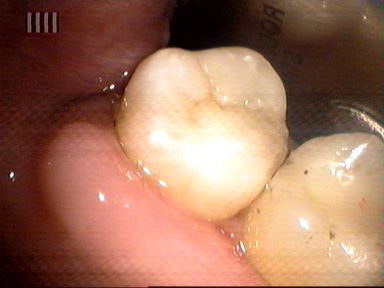

Leczenie próchnicy wtórnej ostatniego górnego trzonowca. Ze względu na trudny dostęp ząb odbudowano laboratoryjnie wykonanym wkładem kompozytowym.